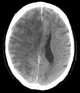

Venous cerebral infarction

Cerebral venous sinus thrombosis (CVST) is the presence of a blood clot in the dural venous sinuses, which drain blood from the brain. Symptoms may include headache, abnormal vision, any of the symptoms of stroke such as weakness of the face and limbs on one side of the body, and seizures. [Source: Wikipedia ]